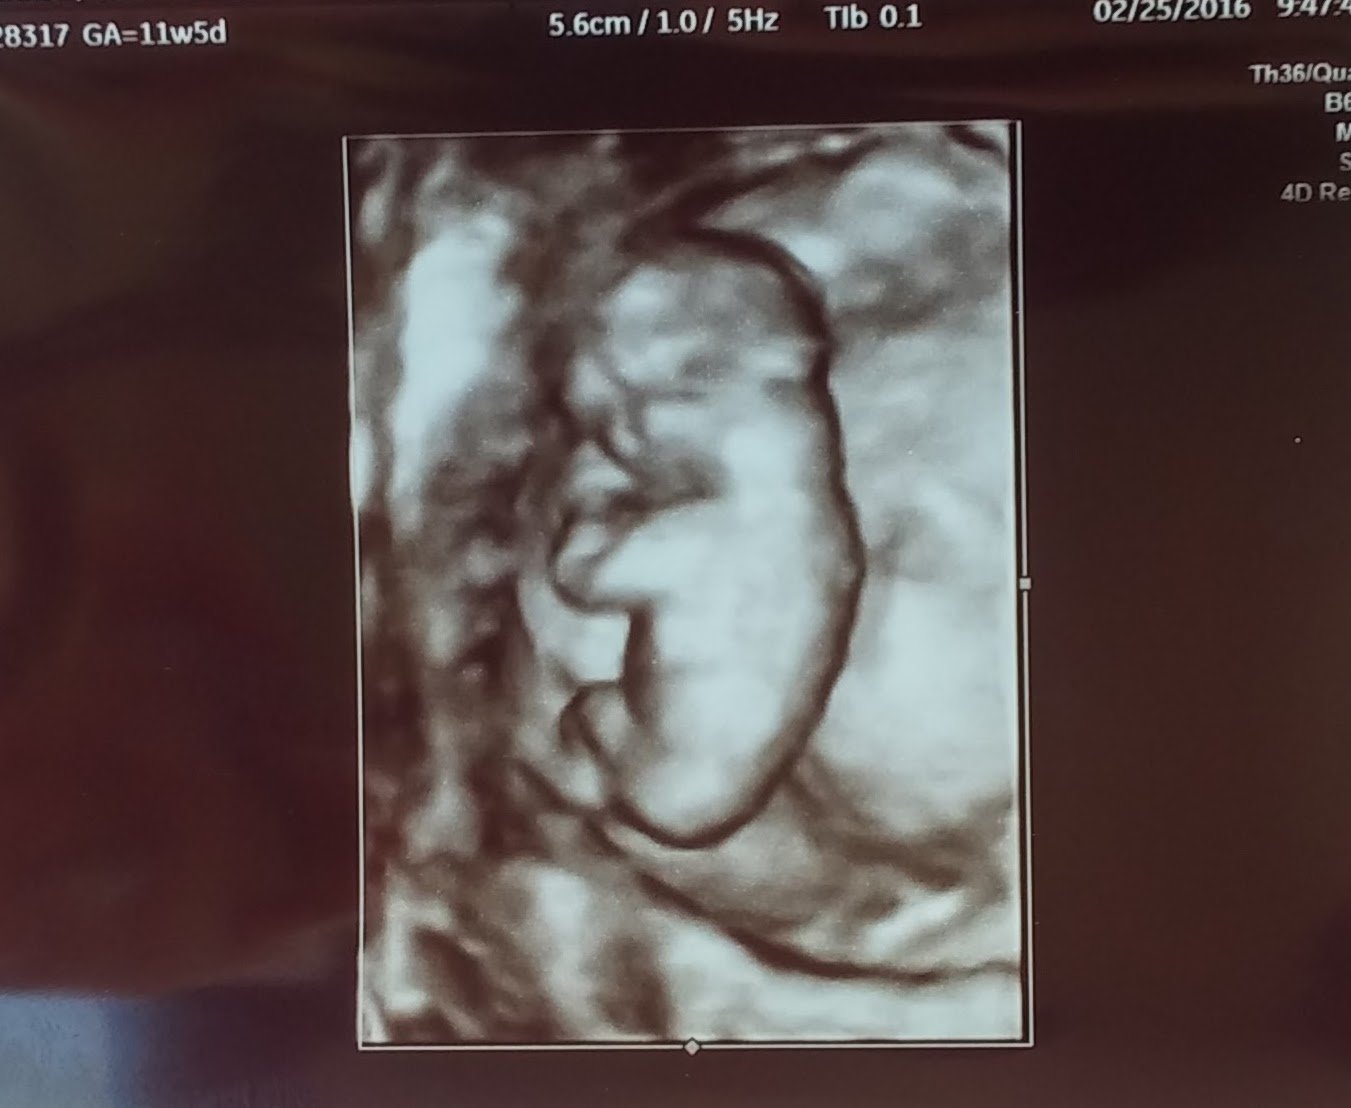

11w6d heart rate is 167 and we are in love!!! "She" (thinking pink) was moving around like crazy!!